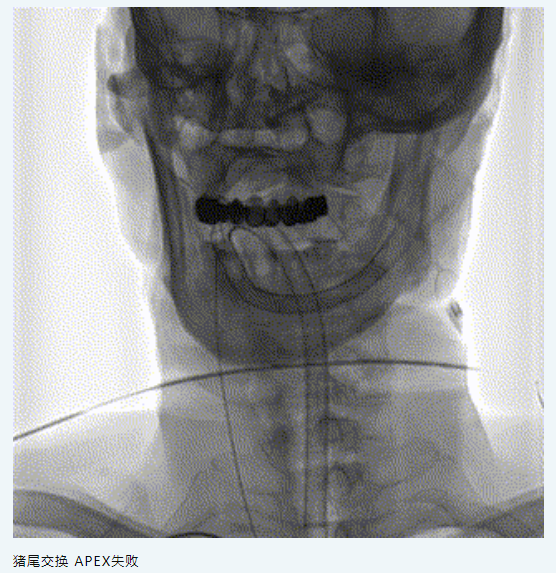

【伙伴喜訊】應用APEX 081橈系統(tǒng)經(jīng)橈行Neuro LPS低壓球囊聯(lián)合NOVA顱內(nèi)藥物洗脫支架治療頸內(nèi)動脈C6段狹窄

6.7F APEX TRA SYSTEM橈系統(tǒng):1、外徑細(2.32mm),對橈動脈侵擾小,內(nèi)腔大(0.081”):可兼容5F中間導管高到位;經(jīng)橈專用,弓部支撐性較長鞘、導引導管、中間導管、DA更強;APEX橈系統(tǒng)配套有130/140cm長SIM2,長SIM2管同軸治療可避免交換失敗,使顱內(nèi)病變更加便捷。